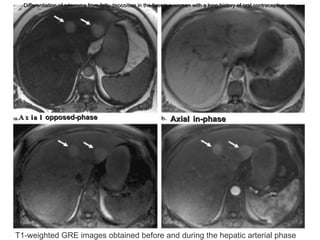

Periportal fat accumulation in a patient with a chronic hepatitis B infection.  Axial unenhanced and late portal venous phase Axial  opposed-phase Axial   in-phase Differentiation of adenoma from fatty deposition in the liver in a woman with a long history of oral contraceptive use. T1-weighted GRE images obtained before and during the hepatic arterial phase

Periportal fat accumulationin a patient with a chronic hepatitis B infection. Axial unenhanced and late portal venous phase Axial opposed-phase Axial in-phase Differentiation of adenoma from fatty deposition in the liver in a woman with a long history of oral contraceptive use. T1-weighted GRE images obtained before and during the hepatic arterial phase